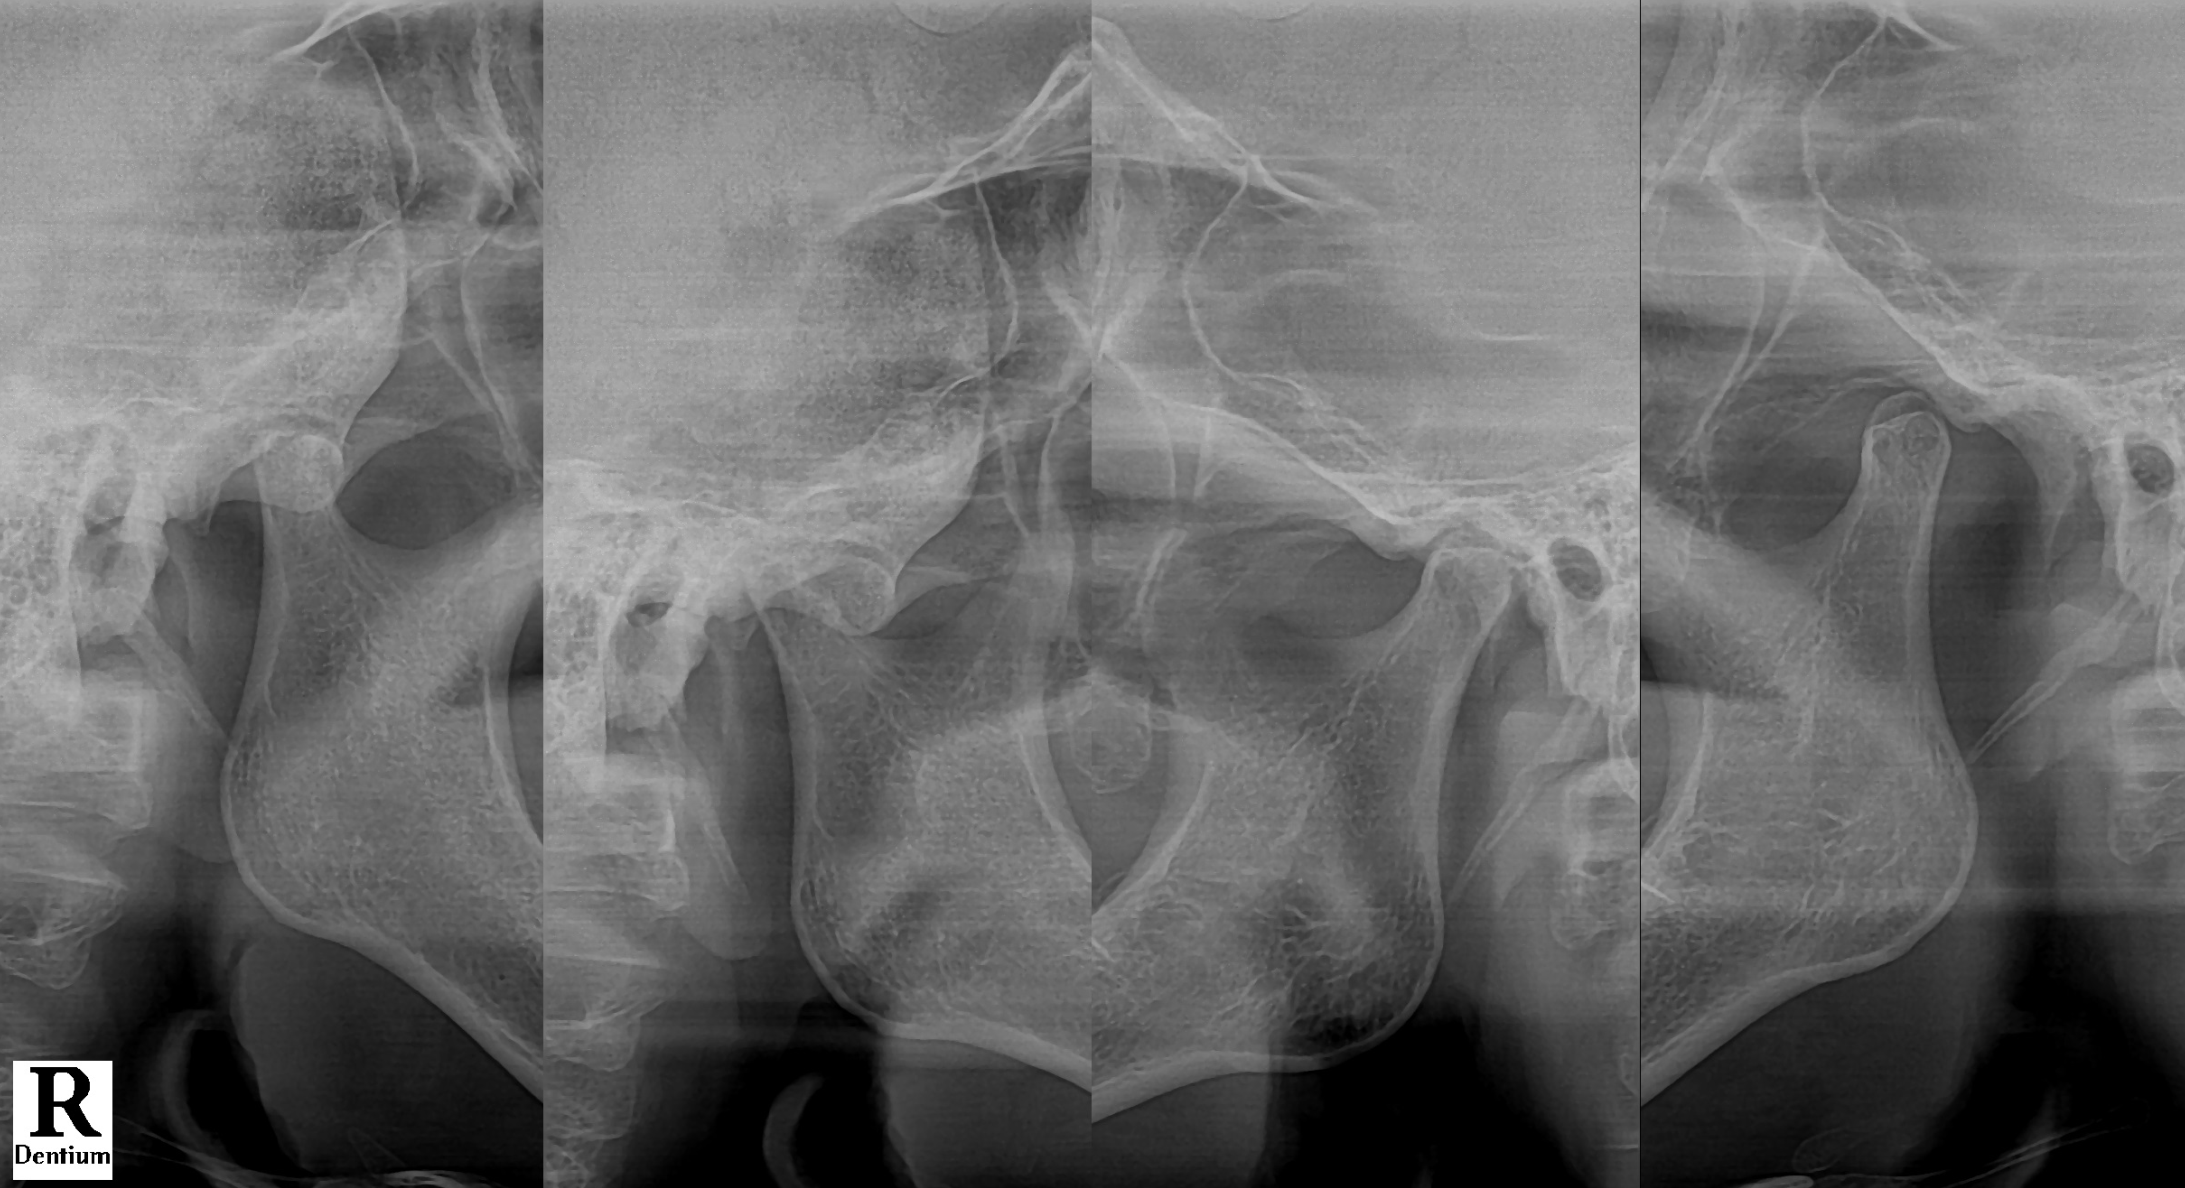

#CaseNo240480 턱이 빠지는 느낌의 시작

이 환자분은 75세 남성으로

가끔씩 씹을 때 오른쪽 턱이 빠지는 느낌이 있었고

그때마다 통증이 동반되었습니다.

최근에는 식사 중 실제로 턱이 빠진 느낌이 있었고,

오른쪽에서 왼쪽으로 손으로 밀어 넣어야

다시 돌아오는 상태였습니다.